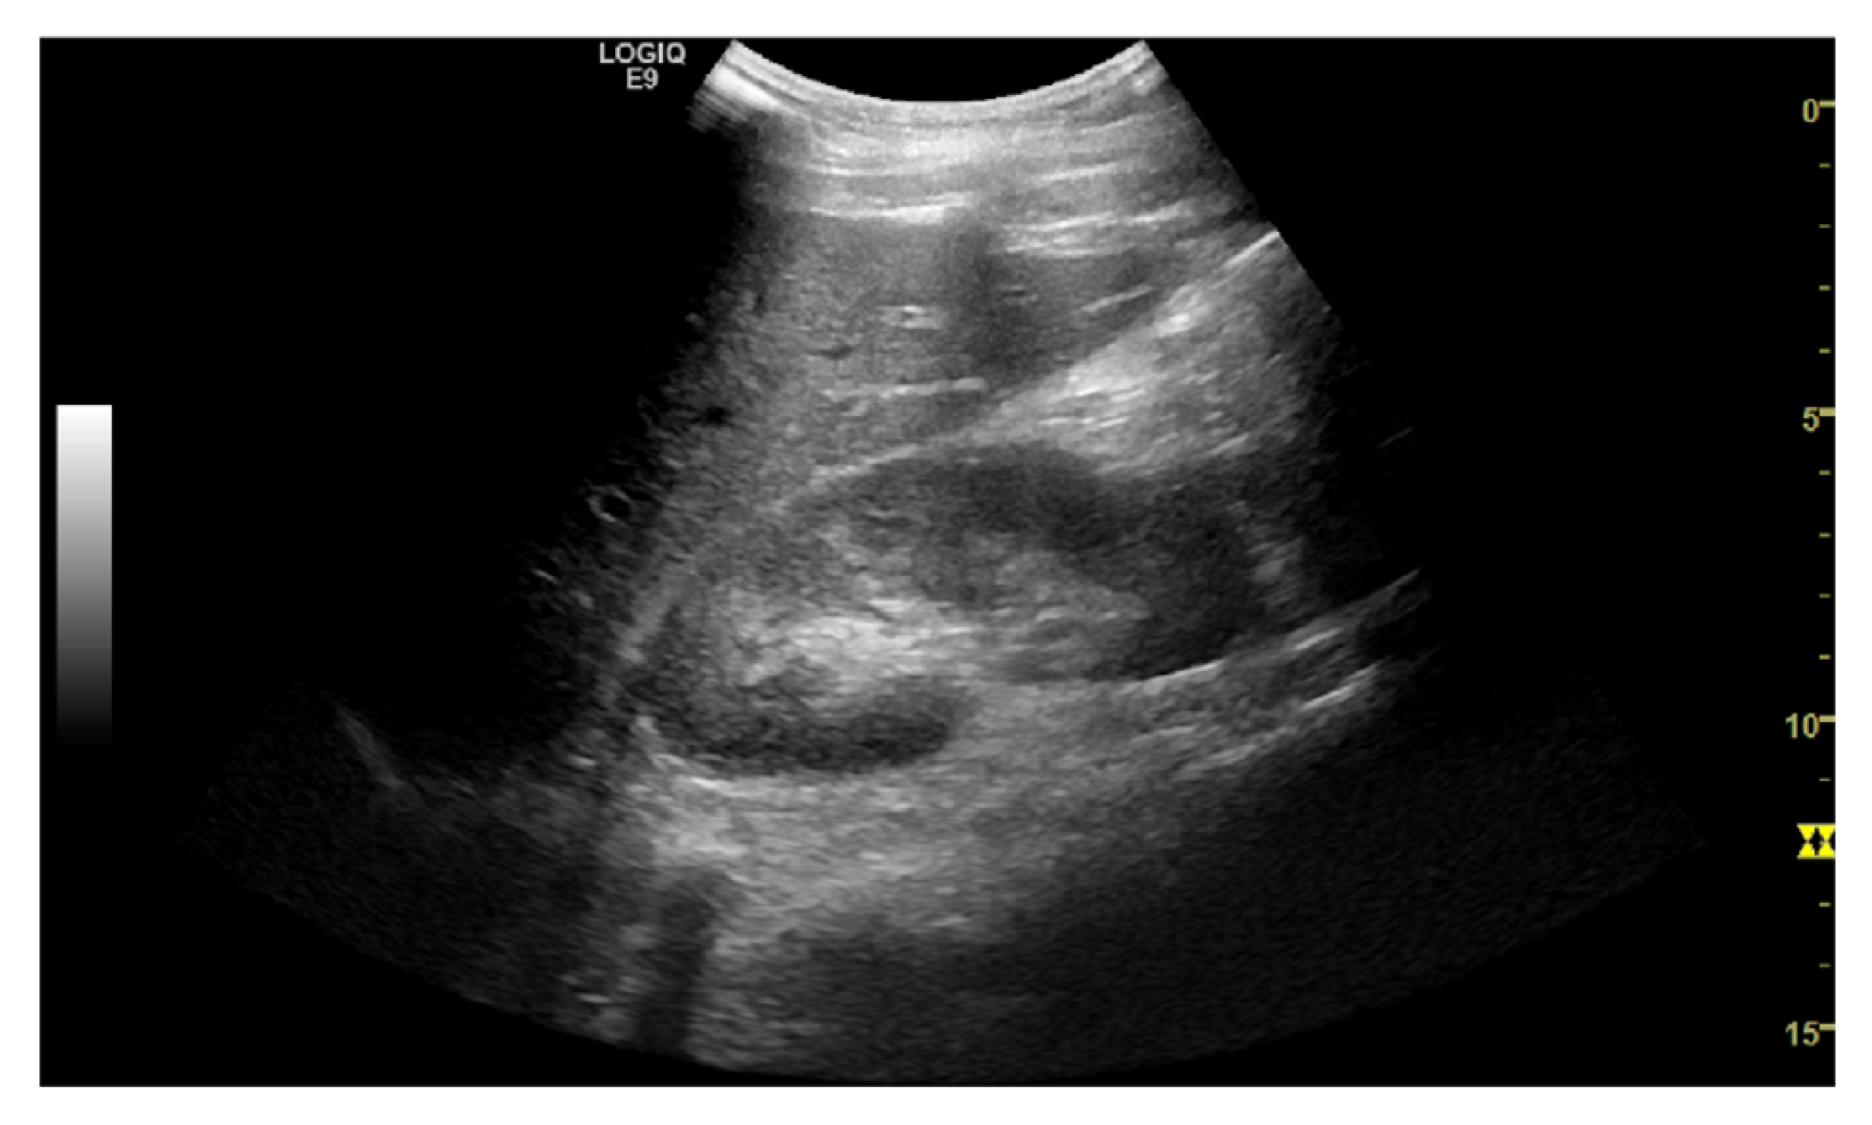

The task is to identify an optimal view for Morrison’s pouch - an anatomic site between the right lobe of the liver and the right kidney. Clinically, the view is important to identify ascites and hemoperitoneum when abnormal fluid accumulation is presented; also, it is the reference view to estimate the severity of steatosis using the hepatorenal index. Therefore, quantifying the view quality is crucial in an ultrasound examination. The images were reviewed by a board-certified radiologist and gave five different rankings as the quality measurement (Figure 4). Class 0 indicates the view does not include the liver or the kidney, and should not be used; while class 4 represent an optimal Morrison’s pouch view that will be used by an experienced operator. We used the ordinal encoding for the labels. (class 0: [0,0,0,0], class 1: [1,0,0,0], class 2: [1,1,0,0], class 3: [1,1,1,0], class 4: [1,1,1,1])

Figure 4: Example of quality score